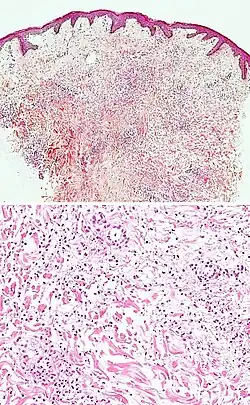

| Prevesicular stage of bullous pemphigoid | Image at right shows influx of inflammatory cells including eosinophils and neutrophils in the dermis (solid arrow) and blister cavity (dashed arrows), and deposition of fibrin (asterisks).[15] However, the diagnosis of bullous pemphigoid consist of at least 2 positive results out of 3 criteria:[19]

|